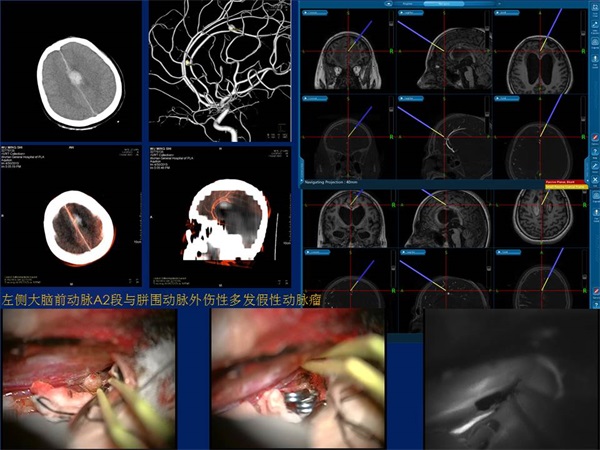

马廉亭,男,80岁,军队专业技术1级教授、博导,文职1级将军,河南安阳人,1954年毕业于安阳师范学校初中第一班、1957年毕业于安阳市第一高级中学、1962年河南医学院医疗系本科毕业入伍,现任广州军区武汉总医院博士后科研工作站站长,曾任中华医学会神经外科学分会常务委员、世界华人神经外科联合会常务委员、全军神经外科专业委员会副主任委员、中南六省(区)及湖北省神经外科学会主任委员、湖北省科技期刊编辑学会副理事长,国家、全军、省、军区及联勤部科技奖及科研基金评审委员会委员,军区、联勤部及医院职称评审委员会委员、主任委员等20多项社会兼职,中华实验外科、中华外料、中华神经外科、觧放军医学、中国临床神经外科等20余种杂志总编、副总编、编委。善长脑神经外科各种疑难病,尤其是脑脊髓血管病的诊治,更精于脑、脊髓血管疾病的血管内治疗,1979年在国际上率先将介入技术应用于颅脑血管战伤的治疗,1983年在国内率先开展血管内神经外科(介入神经放射学),为我国血管内神经外科创建人之一。撰写论著240余篇、主编《脑脊髓血管病血管内治疗学》、《微侵袭神经外科学》、《创伤性假性动脉瘤与动静脉瘘》等连同本书共9部署作,参编《黄家驷外科学》、《手术学全集·神经外科卷》、《临床神经外科学》、《神经病学》等20部著作。获国家科技进步二等奨2项、三等奖1项、省部级与军队科技进步二等奖13项,国家”九五”攻关课题1项、多项省部级及军队科研基金。荣立三等功5次、1998年带领科室参加抢救抗洪抡险伤员生命、为保障部队战斗力做出贡献科室荣立集体二等功、2000年8月29日江泽民主席簽暑通令荣立二等功,享受政府特殊津贴,,获中国医师奨、王忠诚中国神经外科医师终身成就奖、全国优秀科技工作者、全军优秀科技工作者、省科技精英与白求恩式的卫生工作者,2000年将荣获的科技重奖20万元全部捐给医院作为医院培养中青年高端科技人才启动基金、从此医院建立了以【马廉亭】名字命名的医院岀国培养中青年人才奖励基金。多次被中央电视台《祖国在我心中》、《东方之子》及多家报纸、杂志、书刊介绍其先进事迹。75岁退出现役后仍坚持继续在临床从事医教研工作、带领科室同志开展医学影像三维融合技术在神经系统疾病中的临床应用研究,并创造性地研究出"动态三维立体解剖影像融合技术",同時将融合后获得的影像命名为"动态三维立体解剖融合影像”。

《三维影像融合技术在神经系统疾病诊治与研究中的应用》